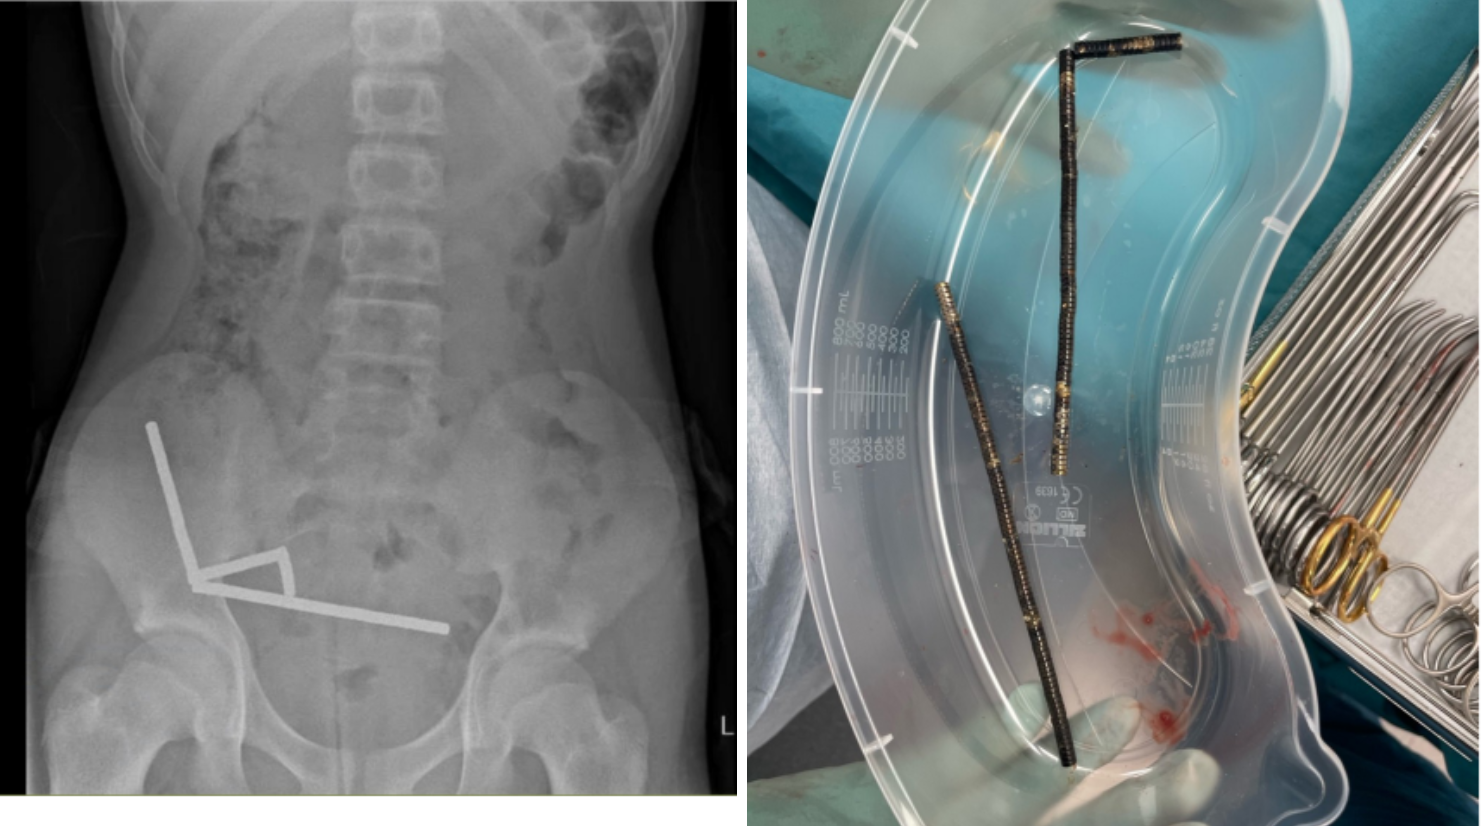

Tras asistir a un centro médico producto de malestares que presentó el menor en la zona del estómago, se percataron que en la radiografía aparecían “cuatro cadenas lineales de imanes” unidas, consigna la revista People.

Eran entre 80 y 100 imanes de alta potencia (neodimio), de 5 x 2 milímetros.

Radio New Zealand agregó que el menor fue tratado en el Hospital de Tauranga. El estudio al menor añade que “la ingestión de cuerpos extraños es común en pacientes (pediátricos)” y agrega que “la mayoría de las ingestiones de cuerpos extraños pasan espontáneamente sin causar lesiones “, sin embargo, “pueden tener consecuencias graves como necrosis por presión, perforación y fistulación”.

Por este motivo, el niño fue sometido a una operación donde le habrían extirpado parte de sus intestinos.

Y es que los riesgos pueden ser graves, como por ejemplo el de este caso, ya que las imágenes mostraron que los imanes “parecían estar en partes separadas del intestino (…) adheridos debido a las fuerzas magnéticas”.